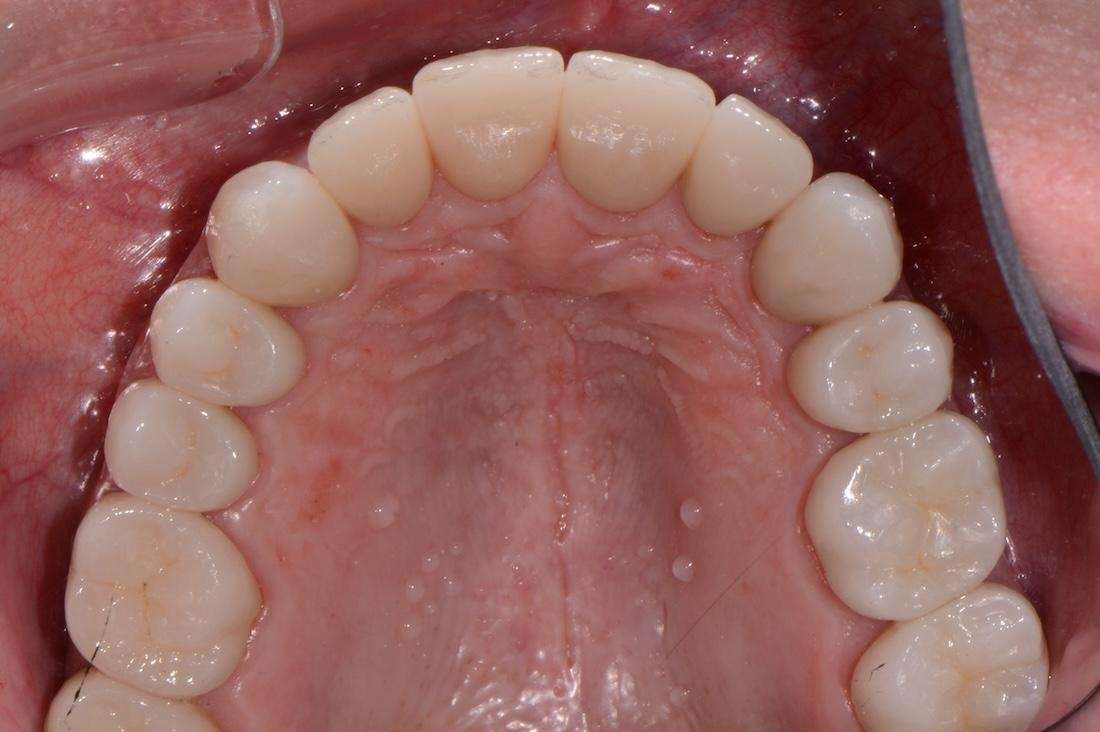

Upper and Lower Porcelain Crown Full Mouth Reconstruction (28 Teeth).

At first, I tried conservative bonding on the upper front teeth, but it simply could not hold up against the patient’s bite issues. After careful planning, I completed a full mouth reconstruction with porcelain crowns. This allowed me to open and correct the bite, restore proper function, and dramatically improve the aesthetics. The final result was a balanced, healthy, and natural-looking smile that gave this patient their confidence back. I especially enjoyed this case because it demonstrates that complex, full mouth reconstructions are not limited to prosthodontists. With advanced training, a general dentist like myself can achieve outstanding results for even the most challenging cases.